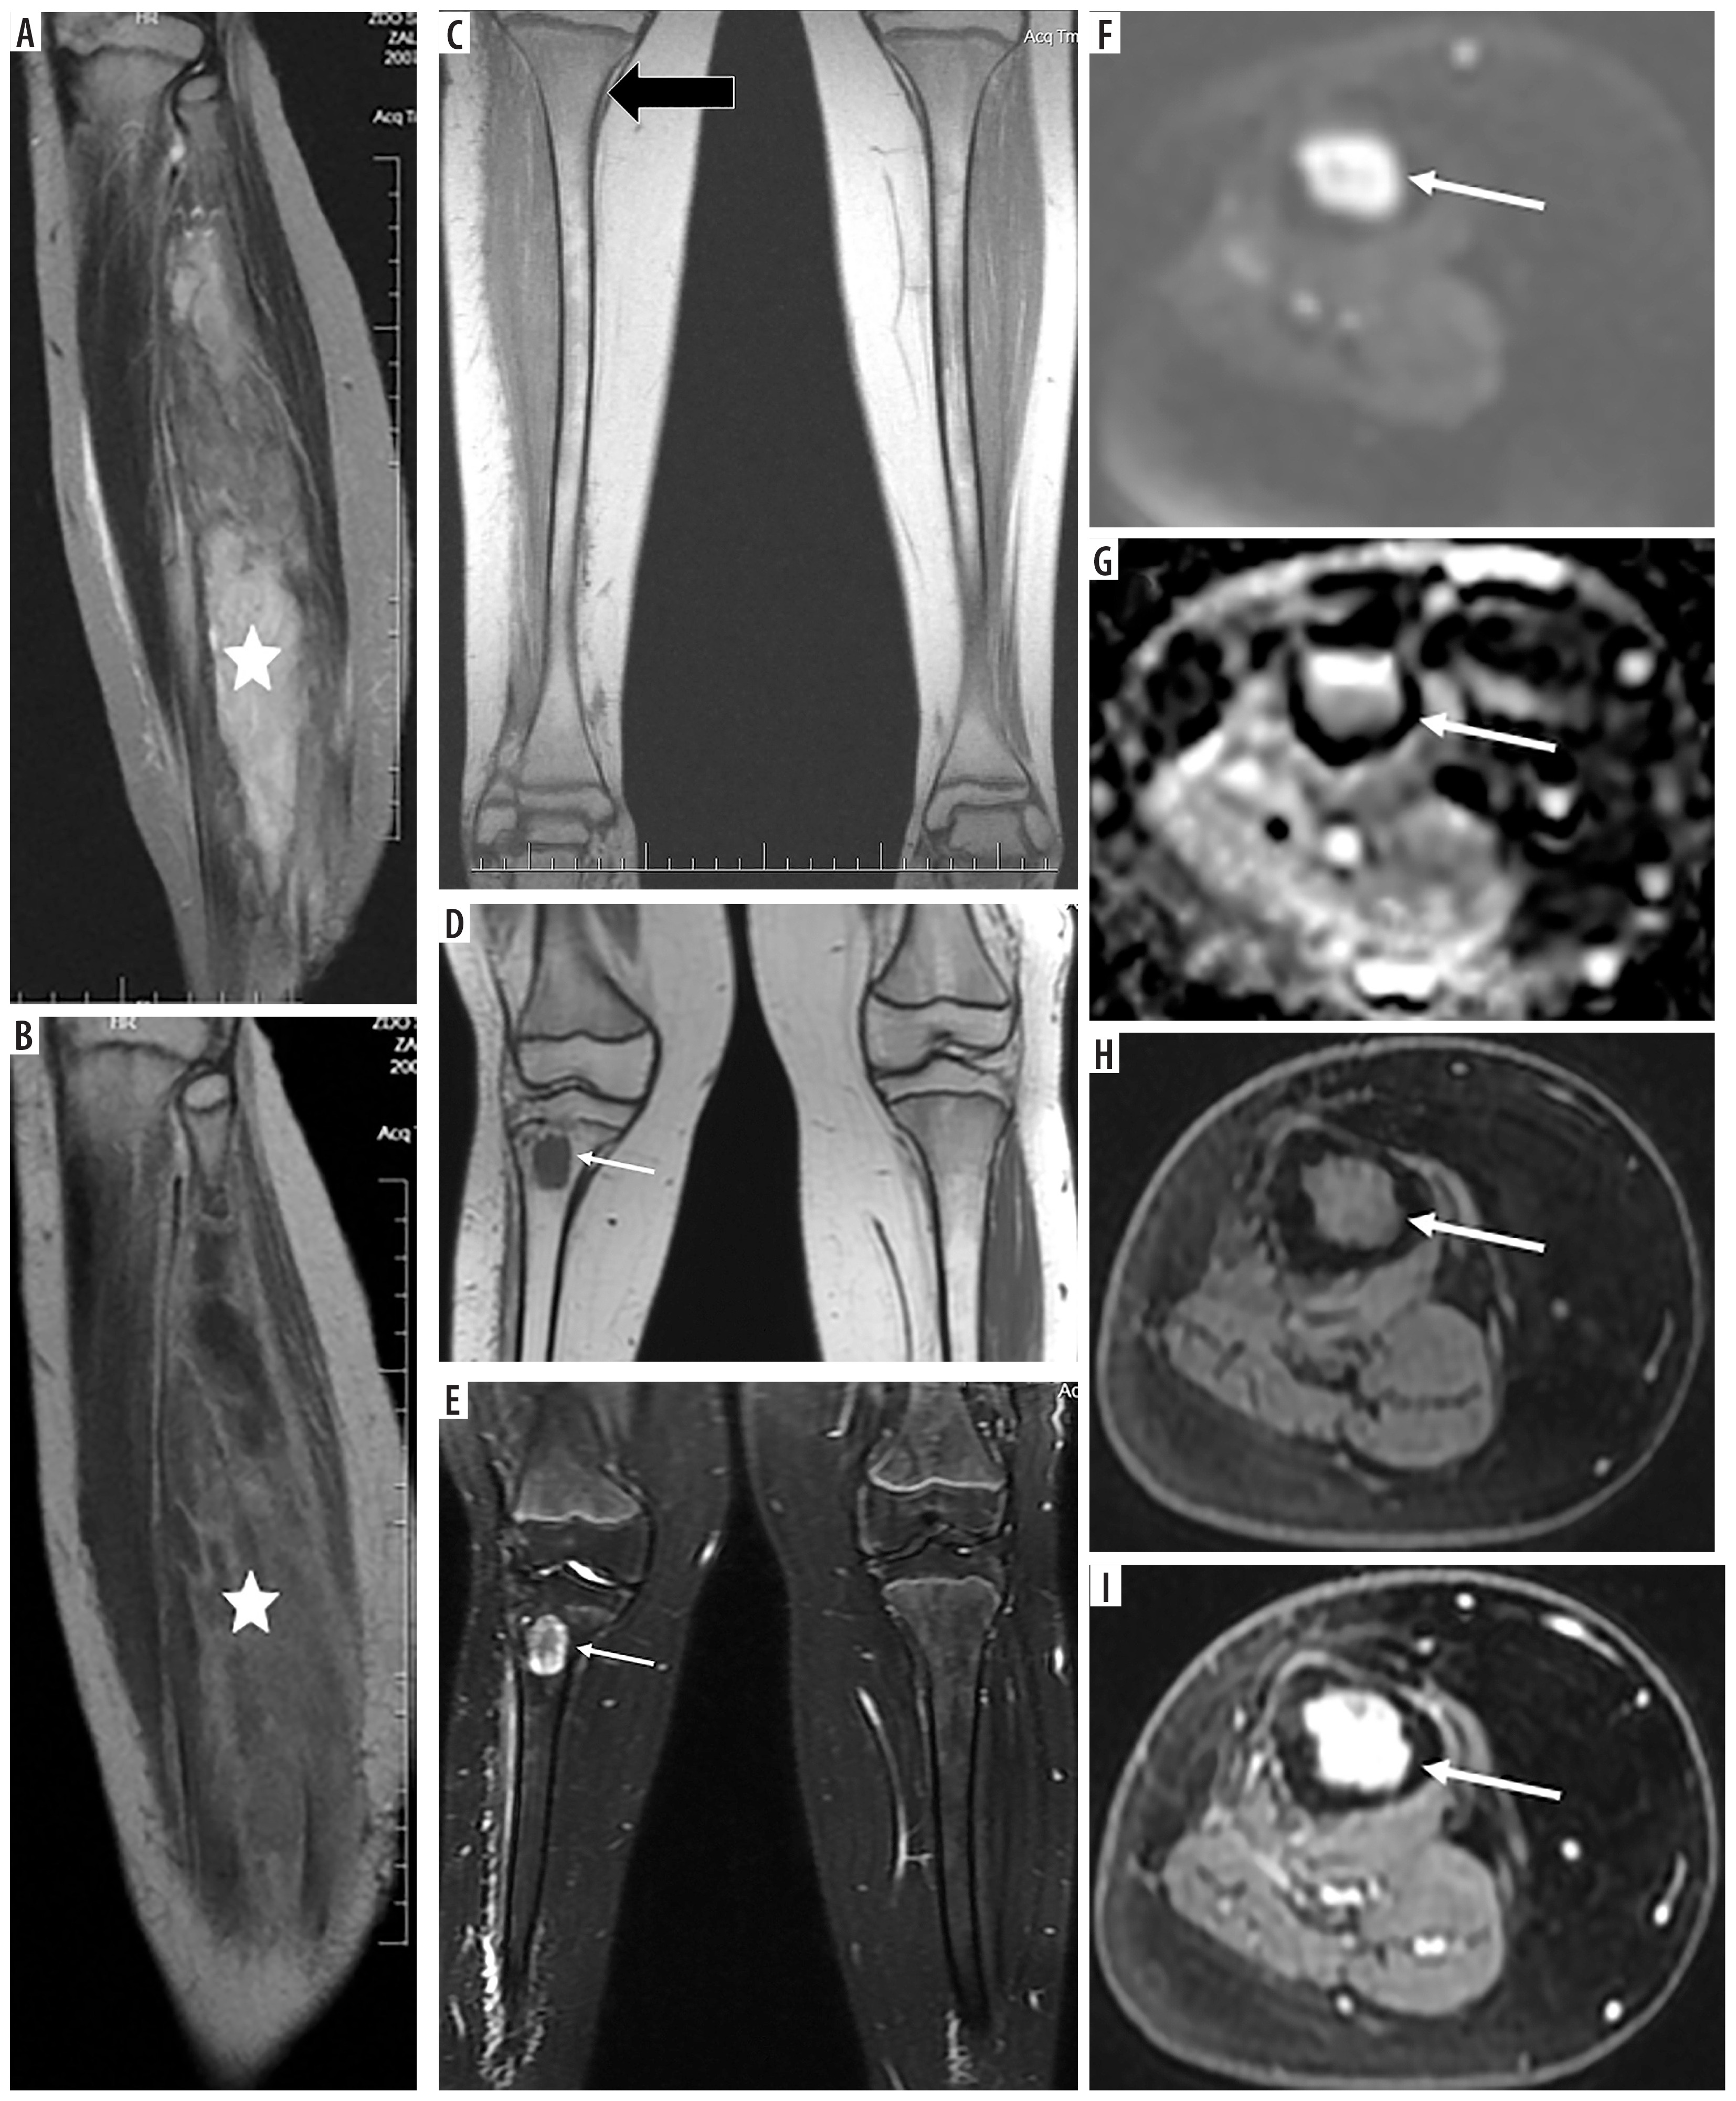

Figure 4

A 14-year-old patient (No. 48) with Li-Fraumeni syndrome. A) Second tumor – high-grade conventional osteosarcoma (HE). B) Third tumor – undifferentiated pleomorphic sarcoma (HE)